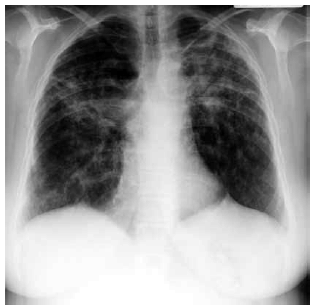

Mulher de 59 anos de idade relata quadro de fadiga, tosse seca e dispneia aos esforços há 1 ano. Nega antecedentes mórbidos, etilismo ou tabagismo. Ao exame físico: PA: 130 x 80 mmHg, FC: 88 bpm; FR: 20 ipm, SatO2: 94% e T: 38 ºC. cardiopulmonar: NDN. Exames séricos: creatinina: 1,1 mg/dL, glicemia: 82 mg/dL, cálcio 11,5 mg/dL (normal: 9 a 10,5), fósforo: 4,7 mg/dL (normal: 3,0 a 4,5), hormônio da paratireoide < 10 pg/mL (normal: 10 a 65) e 1,25-dihidroxivitamina D elevada. Teste cutâneo de tuberculina (PPD) é normal. A radiografia de tórax realizada é mostrada a seguir.

Com os dados descritos, o diagnóstico mais provável é